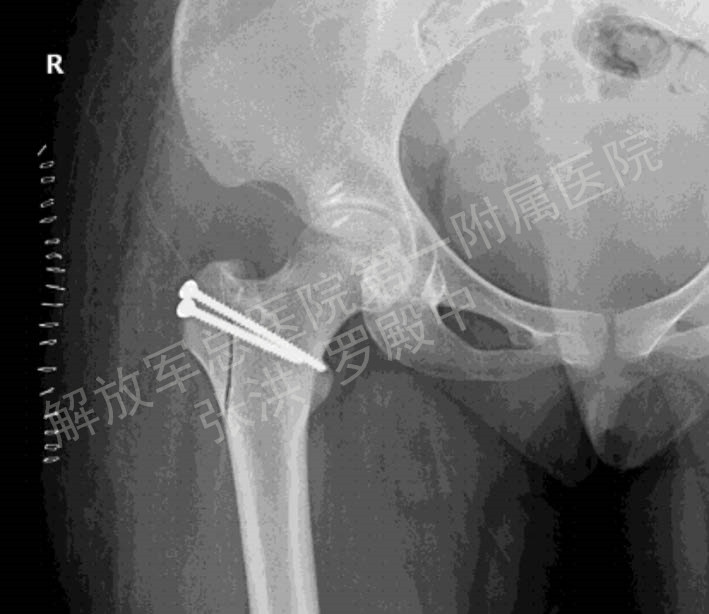

3.4 髋关节脱位合并股骨头骨折

髋关节脱位合并股骨头骨折是髋关节常见创伤之一,既往采用牵引复位、后侧入路的切开复位均有较高的股骨头坏死率。急诊条件下,经SHD 行股骨头骨折切开复位、清理髋关节内碎屑、处理髋臼后壁、复位固定股骨头骨折片,股骨头血运得到最大限度地保护,创伤性关节炎和股骨头坏死率降至最低水平。见图3。

图3 患者男,41岁,左髋后脱位合并股骨头骨折,经牵引髋脱位已复位,但股骨头骨折错位仍明显;经髋关节外科脱位手术入路行股骨头骨折复位内固定手术摇3A 术前螺旋CT 3D重建图片,3B 复位固定后正位X线片